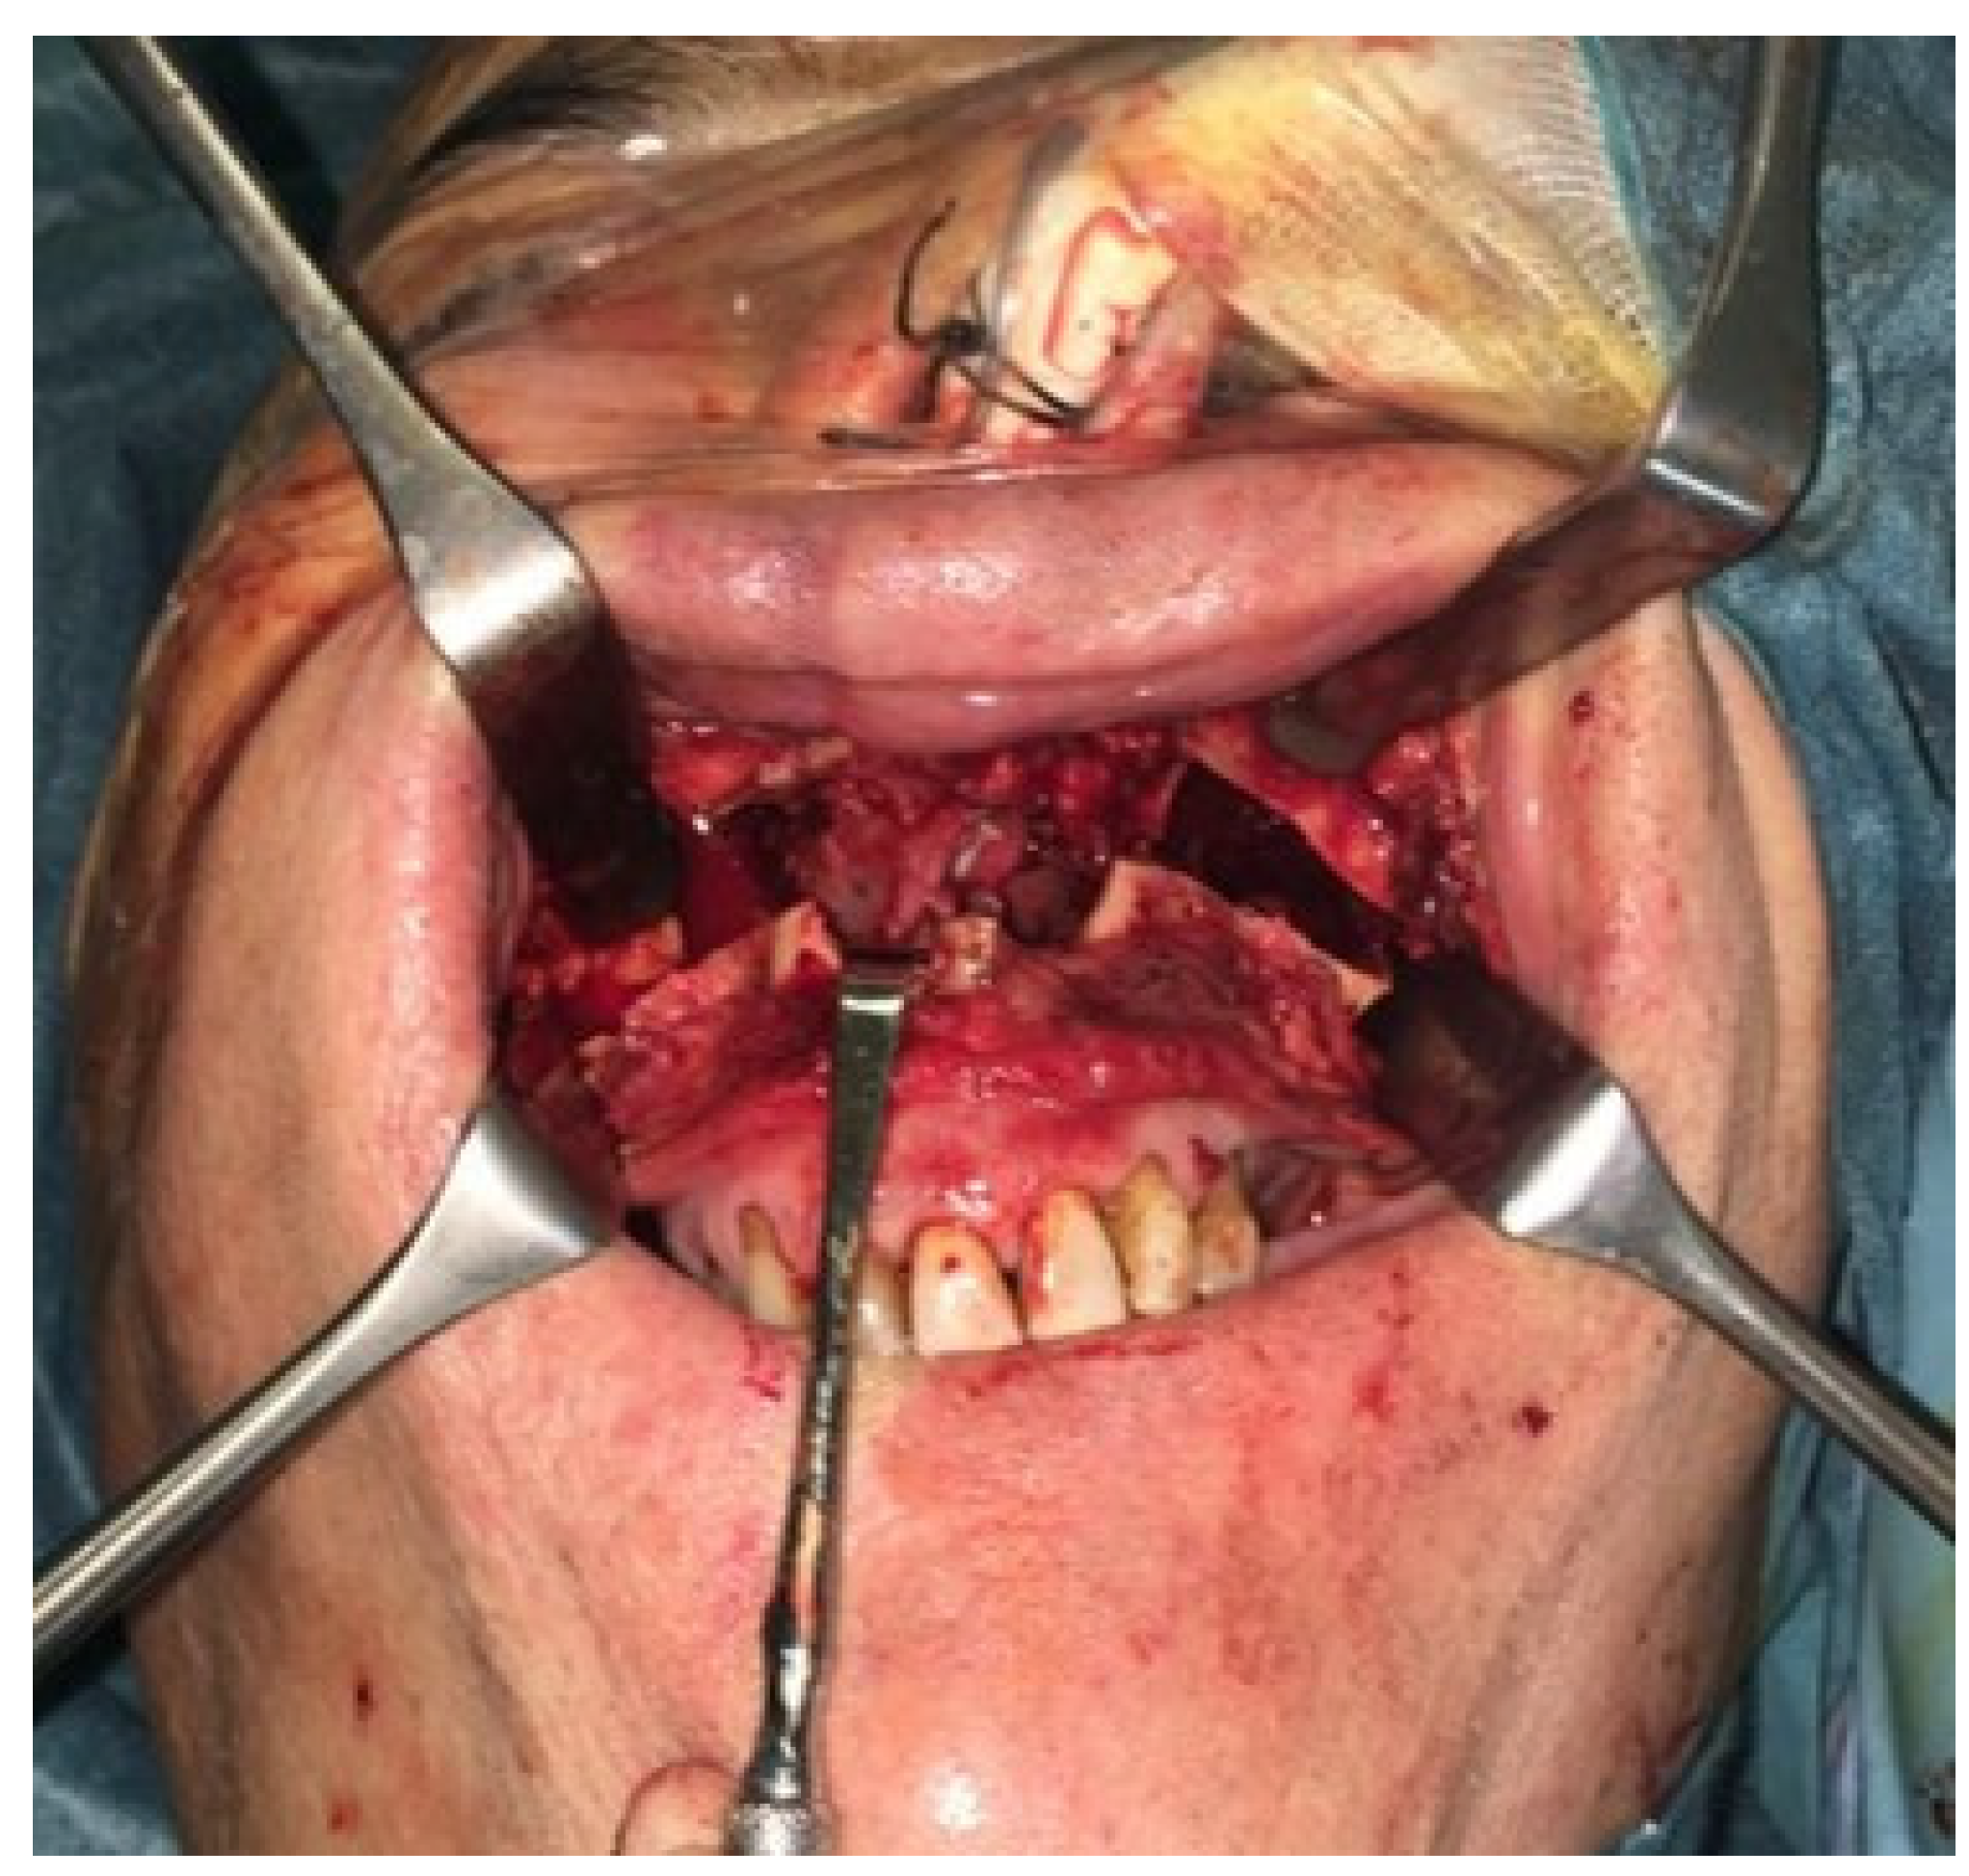

In 2022, after 2 years of sobriety, the patient underwent surgical intervention for palate reconstruction. Under general anesthesia, the surgery was performed, starting with a Le Fort I osteotomy preceded by preplating to achieve the correct repositioning of the fragment. A careful dissection of the nasal and palatal mucosa was performed after the down fracture. A temporalis muscle rotation flap was harvested on the left side (Figure 2). The operation lasted three hours in the oro-tracheal tube. A nasogastric tube was placed and kept in place for seven days with standard antibiotic and anti-inflammatory therapy. The patient was discharged after four days.

Figure 2. (A) The surgery was performed using a Le Fort I osteotomy preceded by preplating to achieve the correct repositioning of the fragment; a careful dissection of the nasal and palatal mucosa was performed after the down fracture. (B,C) Temporalis muscle harvesting and rotation (D,E) fixation of the maxillary fragments.

In 2018, after 4 years of sobriety, the patient underwent surgical intervention for palate reconstruction. The Le Fort I osteotomy was preceded by preplating to achieve the correct repositioning of the fragment (Figure 5). A careful dissection of the nasal and palatal mucosa was performed after the down fracture. A temporalis muscle rotation flap was harvested on the right side. The operation lasted three hours in the oro-tracheal tube. A nasogastric tube was placed and kept in place for seven days with standard antibiotic and anti-inflammatory therapy. The patient was discharged after four days.

Figure 5. The surgery was performed, using a Le Fort I osteotomy preceded by preplating to achieve the correct repositioning of the fragment; a careful dissection of the nasal and palatal mucosa was performed after the down fracture.